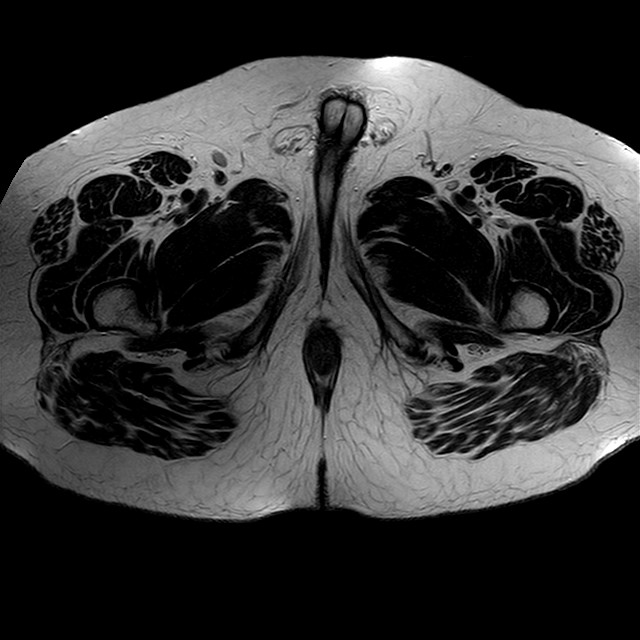

Esami: RMN BACINO

eT2w TSE

Evidenti e simmetriche alterazioni osteofitosiche in regione coxo femorale con riduzione delle rime articolari. Degenerazione completa del cercine glenoideo. Non attuali segni di versamento articolare. Non segni di edema osseo che escludono attuale algodistrofia od osteonecrosi. Lieve e simmetrica riduzione del trofismo della muscolatura glutea.